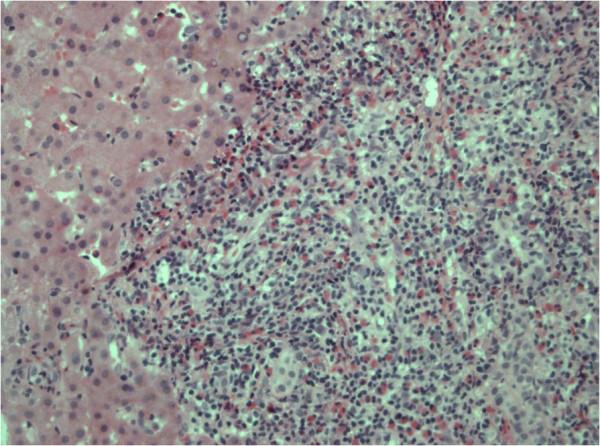

We present a patient with a history of non seminoma of the testis and bleomycin-induced pneumonitis. During follow-up, regression of the hypothesis of eosinophilic migration to the liver after regression of bleomycin-induced pneumonitis is highly suspicious based on transient eosinophilia and focal eosinophilic liver disease.

As follow up may consist of CT scanning in germ-line tumor patients, transient eosinophilic liver lesions reported during regressive bleomycin-induced pneumonitis should not be presumed automatically as metastatic tumor relapse and require further sequential imaging and pathological examination.